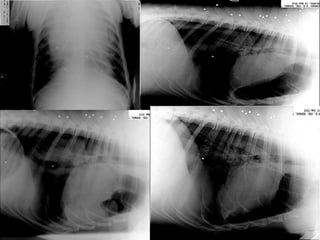

• 63.

«БОРМАН»  Порядочный кобельнемецкой овчарки возрастом 2,5 года  Припеваючи проживает в окрестностях г. Теплодар на закрытой продуктовой базе  Характер дружелюбный и очень общительный, склонен к романтическому разгильдяйству  Свою работу знает хорошо, хотя особо не усердствует  В последнее время внимательно прислушивается к своим инстинктам, особенно – продолжения рода…

• 64.

13.02.2010 «Борман» пошел наповоду у своих инстинктов и самовольно покинул рабочее место, в результате…

• 65.

Истекающий кровью, «Борман»был доставлен в ветклинику для оказания неотложной ветеринарной помощи… Не смотря на полученные травмы, «Борман» пытался самостоятельнопокинуть рабочее место несколько раз. Все попытки вовремя пресекались любящими пса работникамипродуктовой базы. «Бормана» задабриваливсякими вкусностями,но… 20.02.2010 «Борман» был доставлен в ветклиникув очередной раз… Попытка сбежать оказалась удачной, но дальше соседского забора «Борман» пройти не смог… Сунув нос под забор, «Борман» ощутил на себе всю любовь соседского ротвейлера «Юрка»…